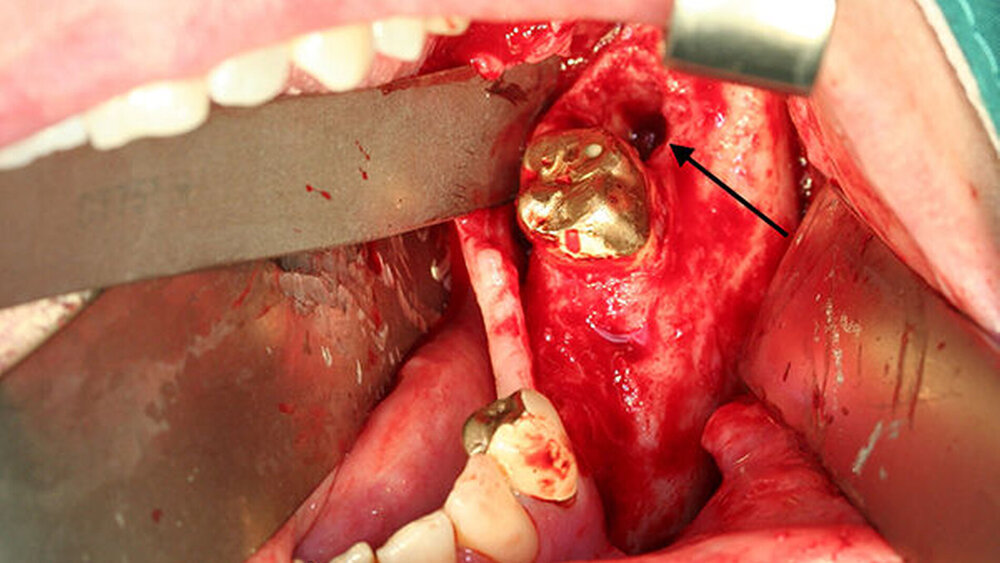

Die Patientin wurde daraufhin bei Verdacht auf eine Unterkiefer-Osteomyelitis stationär aufgenommen. In der Labordiagnostik fand sich ein gering erhöhtes CRP von 1,1 mg/dl (Referenz <0,5 mg/dl) bei normwertigen Leukozyten (7,3 /nl) und bei ansonsten unauffälligen Routine-Parametern. In der durchgeführten CT zeigte sich eine unscharfe, runde Osteolyse regio 038 mit periostaler Reaktion (Abbildung 2).

Insgesamt bestand somit die Indikation zur operativen Revision. Diese erfolgte über einen intraoralen Zugang mit Dekortikation, Entnahme multipler Gewebeproben, Neurolyse des Nervus mentalis links, modellierender Osteotomie und offener Nachbehandlung mittels Tamponade (Abbildung 3).